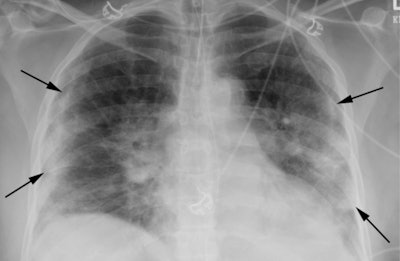

- Characteristic: "presence of bilateral 'patchy' or 'confluent, bandlike' ground-glass opacity or consolidation in a peripheral and mid-to-lower lung zone distribution."

Smith's group found that 10% of chest x-rays showed characteristic COVID-19 appearance, while 57% showed nonspecific appearance and 33% were negative. The two readers had a 92% agreement rate for evaluating the chest x-rays for COVID-19.

The researchers acknowledged that chest x-ray has low sensitivity for diagnosing COVID-19 disease, but they emphasized that it's highly predictive of the illness in patients who have findings that are also characteristic on chest CT.

"We ... observed a chest x-ray pattern in patients during the exponential growth phase of the COVID-19 outbreak in New Orleans ... which is in accordance with the most commonly recognized CT features of COVID-19 in recent literature," the authors concluded. "These observations may be useful for patient triage or may assist in discharge and quarantine planning where rapid and highly sensitive and specific testing is lacking."